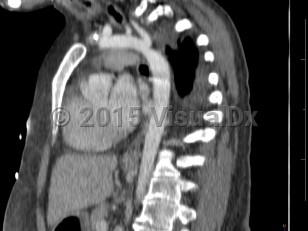

Coarctation of the aorta

Narrowing of the descending aorta distal to the take-off of the great vessels. Posterior costal arteries and internal mammary and scapular arteries provide collateral flow to the descending aorta. Usually congenital, although can be acquired as a consequence of inflammatory diseases affecting the aorta (eg, Takayasu arteritis). Clinical manifestations vary by age and associated cardiac defects, which may include bicuspid aortic valve, atrial septal defect (ASD), ventricular septal defect (VSD), patent ductus arteriosus, and D-transposition of the great vessels.